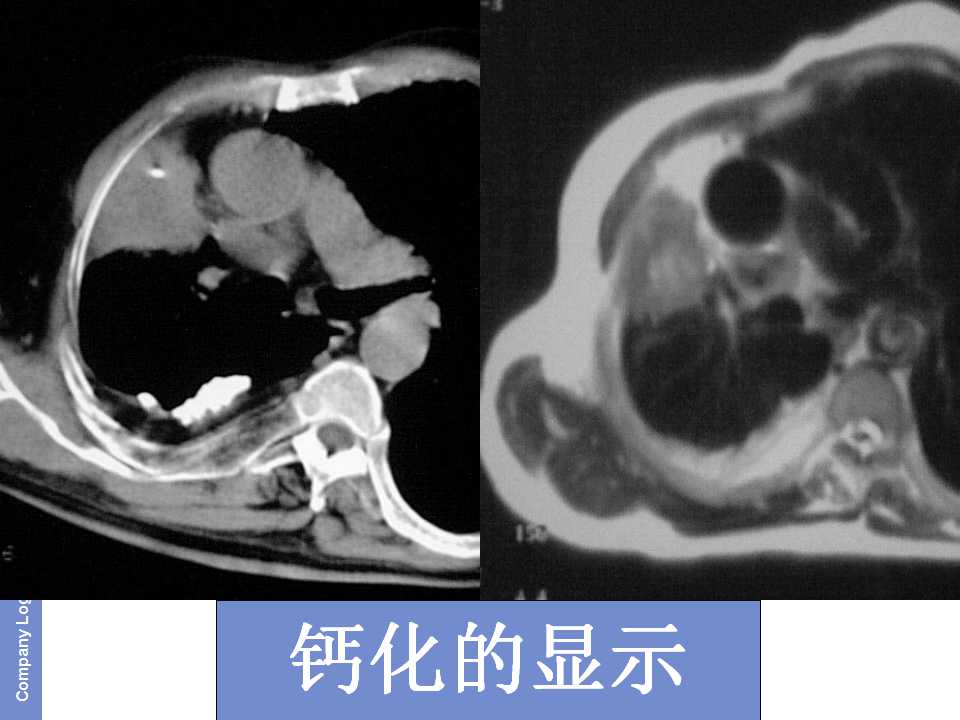

肺癌影像诊断